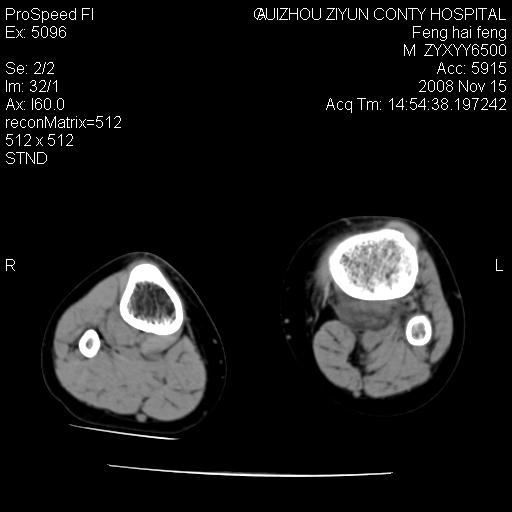

标题: CT16656:M 14Y 左膝关节肿胀一年余。其余病史不详。 [打印本页]

标题: CT16656:M 14Y 左膝关节肿胀一年余。其余病史不详。

考虑左侧髌骨结核;左膝关节滑膜肿胀、增厚,关节囊积液。

左膝滑膜型关节结核可能性大!支持!滑膜型关节结核主要ct表现:关节囊肿胀,积液,关节面见小破坏灶,并见点状死骨!

左膝滑膜型关节结核可能性大!支持!滑膜型关节结核主要ct表现:关节囊肿胀,积液,关节面见小破坏灶,并见点状死骨

好大的左腿!考虑左侧髌骨结核,左膝关节滑膜肿胀、增厚,关节囊积液。

左侧髌骨结核;左膝关节滑膜肿胀、增厚,关节囊积液